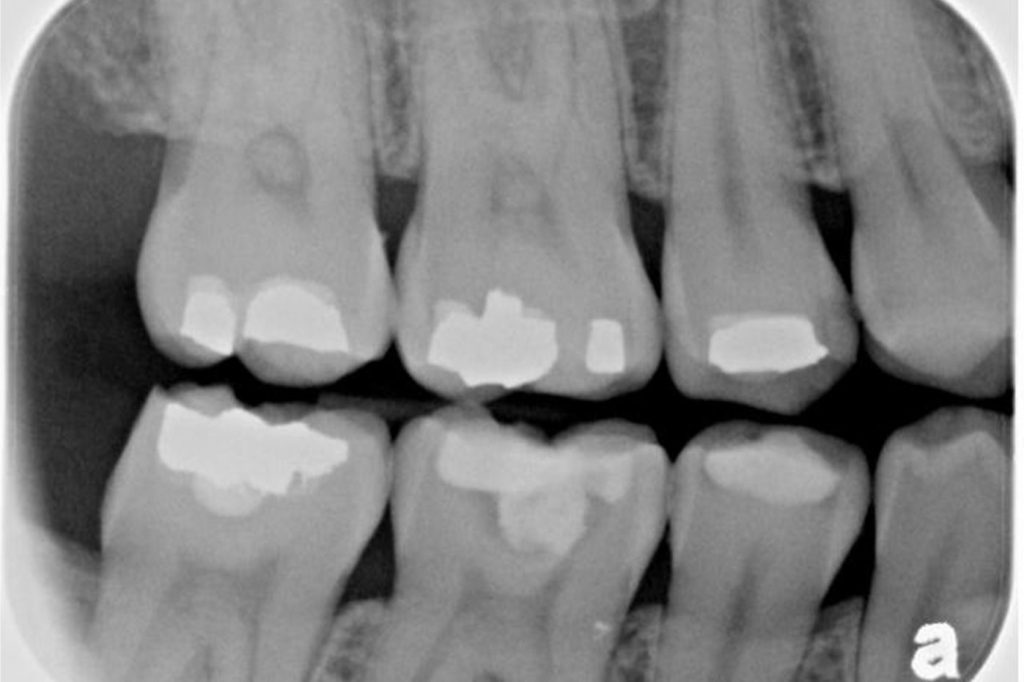

Per la diagnosi delle carie

Alcune carie, soprattutto quelle tra un dente e l’altro, non sono visibili a occhio nudo. La radiografia endorale permette di scoprirle in fase precoce.